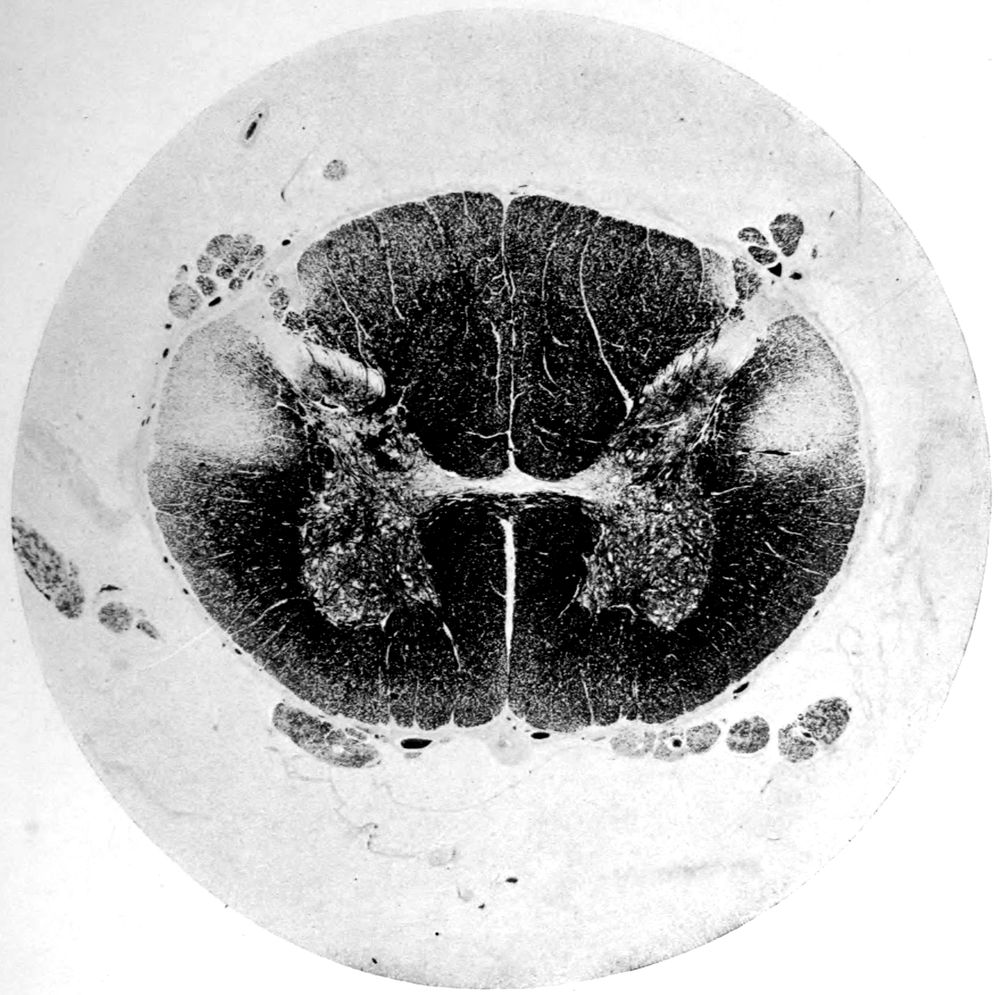

Case 4. (See previous figure for brain lesion.) Three levels of the spinal cord showing unilateral pyramidal tract sclerosis, 10 years after cerebral thrombosis.